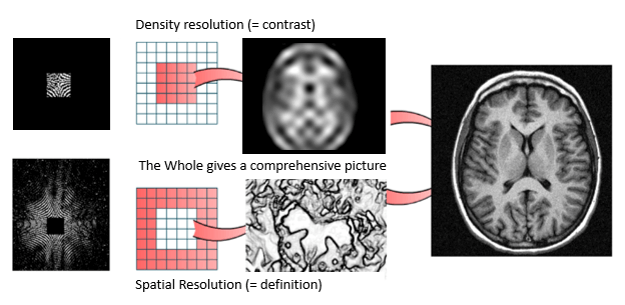

Center and Periphery of the K Space

One of the most important properties of the Fourier space is that the center contains information on contrast and the periphery contains information on spatial resolution. This notion is indispensable for understanding the notion of effective TE and for understanding how filling the Fourier space differently can be used to create specific vascular sequences.

Contrast and Resolution

To summarize, the center of the K space codes for the contrast resolution. Whereas, the periphery of the K space codes for the spatial resolution.

In MRI contrast is a little different. There is no attenuation in the MRI. In MRI many factors control signal and contrast. Contrast is first controlled by TE and TR, resulting in Proton Density, T1 or T2 weighted contrast. Image Contrast is also determined during the filling of the center of K space. By definition, contrast is the ability to differentiate differences in signal intensity of adjacent tissues.

- The center of the K space codes for the contrast of the image, the periphery codes for the spatial resolution of the image